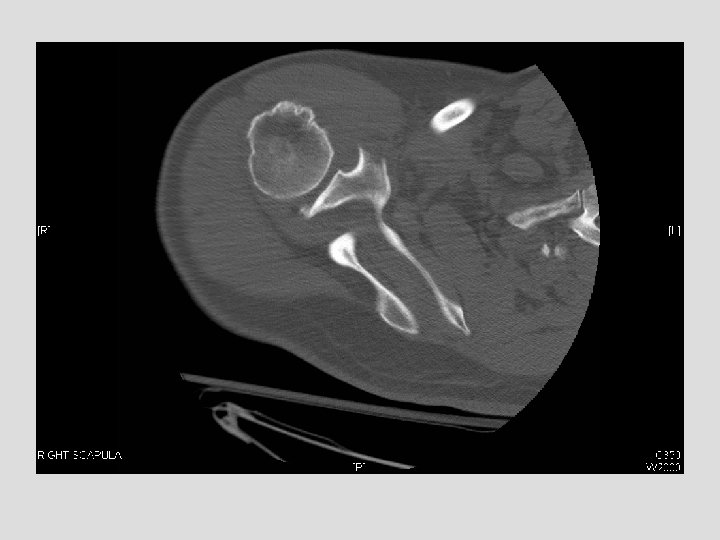

Findings and Differentials Findings: On the CXR, there is a piece of bone overlying

Findings and Differentials Findings: On the CXR, there is a piece of bone overlying the right scapula, which could easily be missed. The follow-up shoulder series and CT more clearly demonstrate a fracture. The CT clearly shows the donor site to be the coracoid process. Differentials: • Coracoid avulsion fracture

Discussion Patient’s that have seizures are prone to shoulder dislocations and put abnormal stress on other muscles. This case is not the typical pattern of injury in a seizure patient, but probably resulted from abnormal muscle contraction; the pectoralis major and minor forcefully contracted, and in this case the minor stressed its attachment to the coracoid such that it resulted in this injury. Ogawa et al. proposed a classification of coracoid fractures based on extent and relation to coracoclavicular ligamentous attachment. Type I is more common and involves the base of the coracoid and is associated with more extensive shoulder injuries and Type II involves the coracoid process itself (this case) and may be an islolated injury. Brant, W. , Helms, C. Fundamentals of Diagnostic Radiology, 2 nd Ed. 1999. Lippincott, Williams and Wilkins. Ppgs. 1001 -1015. Harris. The Radiology of Emergency Medicine, 4 rth Ed. 2000. Lippincott, Williams and Wilkins. Ppgs. 331 -335.